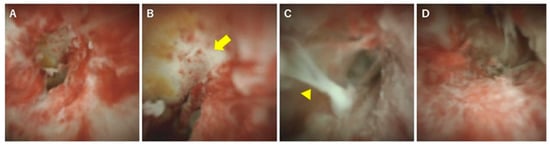

4. POCS for Diagnosing PSC

5. The Phases of PSC and Cholangioscopic Findings in Each Phase

6. Diagnosis and Classification of PSC Using POCS